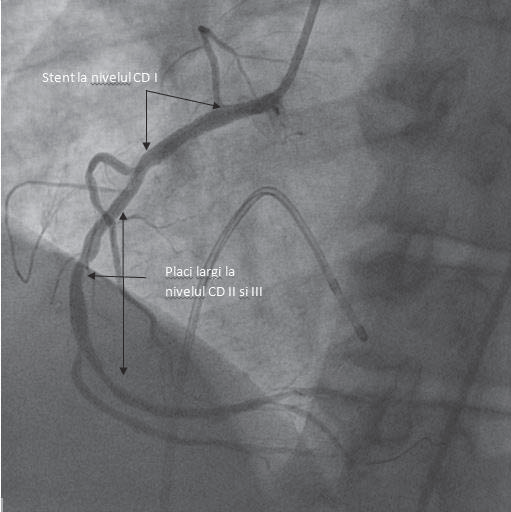

I E, woman, 73 years old, presentation at 8:15 pm. Diagnosis: Acute coronary syndrome with ST segment elevation in the inferior-posterior-lateral territory at 9 hours Killip class I, Thrombolysis 6 hours after onset with reperfusion criteria, Mild mitral regurgitation, Grade II essential hypertension with high additional risk, Obesity, Dyslipidemia, Diabetes controlled by diet Cardiovascular risk factors: Arterial hypertension, dyslipidemia, obesity, diabetes. Retrosternal pain onset 9 hours before presentation, she was diagnosed with myocardial infarction, with ST-segment elevation in the inferior-posterior territory that was thrombolysed 6 hours of onset, with clinical and electrical reperfusion criteria, she is sent to our clinic within the STEMI program. Clinical examination on admission: good general condition, conscious, cooperative, BP=130/80 mmHg, HR (heart rate)=55/min, without cardiac murmurs, without pulmonary or systemic congestion. ECG on admission: sinus rhythm with HR (heart rate)=55/min, ST-segment elevation in DII, DIII, AVF, V5-V9, decreased by approx. 50% compared to the initial ECGs. Laboratory tests: positive troponin (47.5 ng/ml). Echocardiography on admission: EF=50%, posterior wall and lateral will akinesia, mild mitral regurgitation. Coronary angiography reveals 80% stenosis of RCA in the proximal and medial segment, primary angioplasty is performed with 2 stents at the level of the lesions with a good final result, without peri-procedural complications. She has remaining lesions, 70% stenosis on ADA I and another 50-60% stenosis on ADA II. Evolution was favorable, without angina, without heart failure symptoms. The patient will return at a later time for the revascularization of the remaining lesions.

CASE 11

M D man, 50 years old, presented at 10:45 pm. Diagnosis: Acute coronary syndrome with anterior ST elevation at 2,5 hours Killip class II, Grade II Mitral regurgitation, Acute coronary syndrome without ST-segment elevation (NSTEMI)(04.2013) – angioplasty with stent on ADA-04.2013, Chronic smoking, RBBB with uncertain onset, Obesity, Newly discovered Type II Diabetes. Cardiovascular risk factors: smoking, arterial hyper tension, obesity, type 2 diabetes. Pathological personal history: N-STEMI and angioplasty with BMS stent (stent metal bars) on the ADA II in 04.2013. Suddenly installed retrosternal pain, accompanied by diaphoresis for about 2 hours and 30 minutes. Note that the patient has discontinued for the last 6 months, out of his own initiative, the treatment with aspirin and clopidogrel.